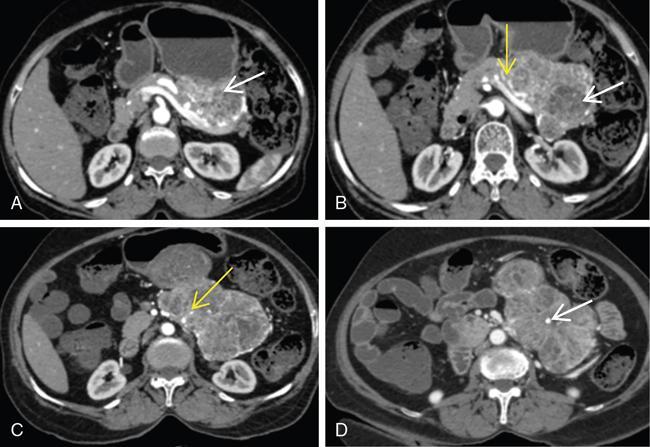

Ritu K. Kashikar, Shrinivas B. Desai, Pooja Punjani Vyas, Nilesh Doctor, Vivek Shetty Advancement and extensive use of imaging in recent times has to lead to increased detection and recognition of cystic pancreatic masses. Imaging however, plays a vital role in noninvasive diagnosis of these lesions, avoiding unnecessary intervention and planning management and follow up guidelines. The aetiology of pancreatic cysts ranges from primary cystic neoplasm to cystic degeneration of solid neoplasm to nonneoplastic cysts (Table 9.19.1). Cystic tumours of the pancreas comprise around 10%–15% of cystic lesions of the pancreas. The aim of this chapter is to educate the reader regarding imaging features of cystic lesions of pancreas, how to differentiate between cysts which can be left alone and those that require further management and also emphasize on latest international guidelines used in stratification of these lesions. Cystic pancreatic lesions are often incidentally detected on USG abdomen performed for other reasons. Although USG is an excellent modality for evaluation of cystic lesions elsewhere, it is unable to adequately characterize pancreatic cysts due to retroperitoneal location of the organ and other confounding factors such as obesity and gases. Most lesions detected on USG require characterization with either MDCT or MRI with MRCP. CEUS improves accuracy in the differentiation between a solid and a cystic lesion and also in determining whether enhancing septa or nodules are present within the cystic lesion. Currently USG also does not have a role in follow up algorithms of pancreatic cystic lesions. Multidetector CT evaluation of pancreatic lesions is best performed with a multiphasic technique (Table 9.19.2). The phases include a precontrast scan, an early arterial angiographic phase, a pancreatic parenchymal phase, and a portal venous phase. The precontrast scan is important for detection of calcification, which may be diagnostic of some lesions. Mucinous cystic neoplasms may be hyperdense on nonenhanced scan suggesting mucin content or haemorrhage. The arterial phase aids in detection of hyperenhancement neovascularity and arterial involvement in pancreatic masses. Optimal parenchymal enhancement of the pancreas is achieved at 35–45 seconds after initiation of injection of contrast agent. This is the pancreatic parenchymal phase. It is in this phase that the tumour pancreas contrast is maximum (Fig. 9.19.1, Table 9.19.3). Most hypoenhancing pancreatic lesions are best detected in this phase. The portal venous phase allows in detection of venous involvement and hepatic metastasis. Delayed phase is typically not required in cystic masses. MDCT has an accuracy of 56%–85% for characterization of cystic pancreatic lesions. MR imaging affords the best noninvasive means for the evaluation of cystic lesions of the pancreas due to superior soft tissue resolution. The helpful distinguishing characteristics of cystic pancreatic lesions, morphology of septae, relation to pancreatic duct are easier to detect at MR imaging and MR cholangiopancreatography (MRCP) than at CT (Table 9.19.4). Studies however indicate that MDCT and MRI are comparable in identifying malignant behaviour of cystic pancreatic lesions. The MRI protocol for evaluation of cystic lesions of pancreas includes T2-weighted single-shot fast spin-echo, T1-weighted in-phase and opposed-phase gradient echo, diffusion-weighted imaging, T2-weighted fat-suppressed fast spin-echo. Three-dimensional T1-weighted fat-suppressed spoiled gradient-echo T2-weighted MRCP. Postcontrast protocol includes dynamic three-dimensional T1-weighted fat-suppressed spoiled gradient-echo (in arterial, pancreatic and portal venous phases) (Fig. 9.19.2, Table 9.19.3). DWI has not found much utility in cystic neoplasms owing to overlap in ADC values. Some studies suggest role in distinguishing malignant from benign tumours in the case of mucinous cystadenoma and IPMN. Secretin is a peptide hormone produced in the intestinal mucosa, which stimulates the secretion of bicarbonate-rich fluid into the pancreatic ducts and transiently increases the tone of the sphincter of Oddi. The increased fluid distention of the pancreatic duct allows better study of ductal anatomy and identifying communication of pancreatic cystic lesions with the pancreatic duct. EUS is excellent in characterization of cystic lesions of pancreas. The proximity between the transducer and the lesions allows precise definition of the structural component of the cysts and components such as small mural nodules are better visualized with EUS than with other modalities. The other advantage of EUS is that cysts fluid aspiration and cytology can be performed. Tumour markers, genetic markers can be evaluated in the aspirated fluid. This allows comprehensive evaluation of cystic lesion. EUS also has therapeutic advantages allowing endoscopic draining of pseudocysts. Recently endoscopic ablation of cysts has been performed. These advantages have led to increasing use of EUS in recent years. This modality is however not indicated in all lesions and imaging should be able to stratify lesions requiring further invasive investigations. Studies have found PET CT comparable to PET alone or CT to determine presence of malignancy in cystic lesions. False positive findings may however be problematic. There is however no consensus for routinely using PET CT in characterization of cystic pancreatic masses. Serum CA19-9 and CEA are routinely done in all pancreatic masses. Though role in cystic lesions is still controversial. Serous cystadenoma is a benign neoplasm composed of glycogen-rich epithelial cells that form innumerable small thin-walled cysts containing serous fluid. It is the prototype microcystic pancreatic neoplasm. They occur frequently in older women (median age, 65 years) and is also called as grandmother lesion. Approximately 40% of pancreatic serous cystadenoma arise from the pancreatic head and uncinate process and 60% arise from the pancreatic body and tail. Serous cystadenomas are usually discovered incidentally at imaging; however, those that are large may cause symptoms. Patients may present with abdominal pain, palpable mass, anorexia, fatigue/malaise, or weight loss. Rarely the patient may present with jaundice. Genetic alterations similar to those in VHL are seen in sporadic SCA and include tumour suppressor gene VHL mutations and overexpression of vascular endothelial growth factor (VEGF). Allelic loss in chromosome 3 have seen in up to 40% cases of sporadic SCA. Serous cystadenomas are variable in size. The size ranges from <0.1 to 25 cm. The tumours are grossly well demarcated from the surrounding parenchyma. The gross appearance of the lesions is variable. It could be microcystic, consisting of innumerable small cysts giving the macroscopic appearance of a sponge or honeycomb. The presence of multiple, microscopic SCN is characteristic of von Hippel–Lindau (VHL). This variety show a centrally located area of fibrotic scar. In Macrocystic/oligocystic variant, borders with the surrounding parenchyma are less defined and the cystic lesion generally does not exhibit a central scar. The Solid variant, the lack of cystic spaces on gross inspection often gives the initial impression of a neuroendocrine or solid pseudopapillary neoplasm. Serous cystadenomas show nonviscous, clear-to-yellow cyst fluid, which provides an important clue to the distinction of SN from mucinous neoplasms. In contrast to intraductal papillary mucinous neoplasm, there is no connection with main or branch pancreatic ducts. These are clinically benign pancreatic epithelial neoplasms exhibiting serous morphology, characterized by a monotonous, cuboidal epithelial cell proliferation with marked cytoplasmic clearing due to intracellular glycogen. The centrally located epithelial cell nuclei are uniformly round to ovoid and not particularly large or hyperchromatic. Abundant diastase-sensitive cytoplasmic glycogen is highlighted by a periodic acid–Schiff stain. These lesions do not show evidence of necrosis, infiltrative architecture, or lymphovascular/perineural invasion, and mitotic figures are generally not observed. A variably prominent pseudocapsule of fibrosis divides parenchyma from the neoplasm On USG the microcystic variant shows lobulated contour with multiple tiny anechoic cysts separated by septae. the central scar containing calcification can be seen if present. Extremely microcystic, honeycomb variant may resemble a solid lesion at conventional US. The macrocystic type, can be mixed type with multiple large (>20 mm) and small cysts, and the unilocular type, which is more difficult to differentiate from mucinous cystadenoma (MCA). Enhancement of the intralesional sepatations is seen on contrast-enhanced USG allowing better characterization of the lesion. The central scar can show homogenous enhancement. Honeycomb variety appears as a hypervascular lesion owing to its extremely microcystic morphology and may resemble solid masses like neuroendocrine tumours. Pancreatic serous cystadenoma can have a varied appearance on CT depending on the morphologic patterns. Serous cystadenomas are typically solitary but may be multiple in von Hippel–Lindau disease, causing an appearance of disseminated involvement (Table 9.19.5). As mentioned previously, the polycystic pattern is the most common appearance of serous cystadenoma. A pattern of a bosselated collection of cysts that usually number more than six is seen. Each cyst may range from a few millimetres to 2 cm in size (Fig. 9.19.5). The other classic CT features include a lobulated contour and presence of a central stellate scar with calcification. This scar is seen in 30% cases and when present is strongly suggestive of the diagnosis. The intralesional fibrous septae show early enhancement after contrast administration. This is a distinguishing feature, as serous cystadenoma is the only hypervascular lesion among the cystic pancreatic neoplasms. Tiny cysts mimicking a honeycomb are the hallmark of this variant and may be poorly depicted as individual cysts on CT. On unenhanced CT, the honeycomb pattern may appear as a well-marginated lesion with soft tissue or mixed attenuation, depending on the size of the cysts and the amount of fibrous tissue. Moderate to strong enhancement is seen in these lesions (Fig. 9.19.6). This appears as a unilocular cyst or it may contain fewer large (>2 cm) cysts. Imaging Features include a lobulated contour, lack of a prominent thickened peripheral wall, and location in the head of the pancreas (Fig. 9.19.7). Owing to its supreme soft tissue resolution, MRI is the modality of choice in diagnosis of serous cystadenomas. The classic MRI features of microcystic variant includes a lobulated lesion with multiple small T2 hyperintense and T1 hypointense cysts with intervening hypointense fibrous sepate. These lesions do not communicate with the pancreatic duct; hence no dilatation is usually seen. Dilatation of pancreatic duct has however been reported in larger lesions. After the administration of gadolinium, the hypervascularization of the central scar and of internal septa may be seen. The morphology of the honeycomb pattern may also be better depicted on MRI. Multiple tiny T2 hyperintense cysts with intervening hypointense septae are seen (Fig. 9.19.8). The oligocystic variant shows fewer larger T2 hyperintense and T1 hypointense cysts and can mimic mucinous cystadenoma. However, the lobulated contour, together with the absence of wall enhancement and a wall thickness less than 2 mm, suggest the correct diagnosis (Fig. 9.19.9) (Table 9.19.6). The differential diagnosis of serous cystadenoma depends on the variety and are listed in Tables 9.19.7 and 9.19.8. Lesions with classic imaging features do not require further investigation or fluid analysis. The fluid in classic cystadenomas is yellow in colour and does not show elevated amylase, mucin or tumour markers. Approximately 20%–50% cases show cytological positivity for periodic acid-Schiff and cytokeratin AE1 and 3. Hemosiderin laden macrophages also do not have high diagnostic accuracy and are seen in only about 43% cases. Current management guidelines suggest (Table 9.19.9). Resection involves distal pancreatectomy or Whipples, depending on location of the tumours and is currently reserved for truly symptomatic cases. Mucinous cystic tumours are a rare subset of cystic neoplasms, constituting approximately 2.5% of pancreatic exocrine tumours. TABLE 9.19.10 The defining and characteristic histopathologic feature of mucinous cystic neoplasms (MCNs) is the presence of ovarian-type stroma similar to that observed in biliary cystadenomas. International Association of Pancreatology recommend that all suspected MCNs be surgically resected. A significant female predilection is seen with approximately 99.7% cases seen in women. As opposed to serous cystadenomas these lesions occur in middle aged women and hence the term mother lesions is used to describe these. The approximate age of occurrence is 50 years with a range from 20–82 years. Mucinous cystic tumours are a dominant cyst that is round or oval and is encapsulated. MCNs may grow slowly over time, at an average rate of 4 mm per year. The most common locations are the pancreatic body and tail (up to 75%). Stromal elements similar to ovarian stroma are the hallmark and key feature that aids in differentiation from IPMN, whose stromal elements are ductal in origin. Tall columnar cells with intracellular mucin arranged in a single row or vertically, forming papillary or polypoidal projections, constitute the epithelial elements. Portions of benign appearing epithelium can be seen adjacent to areas of invasive carcinoma in the same tumour. These lesions show smooth contour on gross appearance with few internal sepate. Peripheral calcification, mural nodule if present suggest malignant cyst (Fig. 9.19.11, Table 9.19.11). Lesions may be asymptomatic in 25% cases. Patients my present with pain in abdomen. Mucinous cystadenoma can also present with pancreatitis. Considering most lesions are located in distal body and tail involvement of splenic vein may lead to left sided portal hypertension. Mucinous cystic tumour is a well-circumscribed cystic mass in the pancreas. Lesions can have an irregular contour to the wall, septations, mural nodularity, and peripheral calcifications. The lesion may however be echogenic due to high by mucin content or haemorrhage which may impair the detection of other features. CEUS may improve detection rate of septa and mural nodules. Lesions are typically well-circumscribed with smooth contour. On unenhanced CT, mucinous cystadenoma may appear hypodense or slightly hyperdense content, due to the presence of variable amount of mucin and haemorrhage. Curvilinear calcifications occur along the periphery of the lesion and are seen in 15% of cases, in contrast study enhancement of the fibrous cyst wall along with enhancement of any septations or mural nodules is seen (Figs. 9.19.12 and 9.19.13).